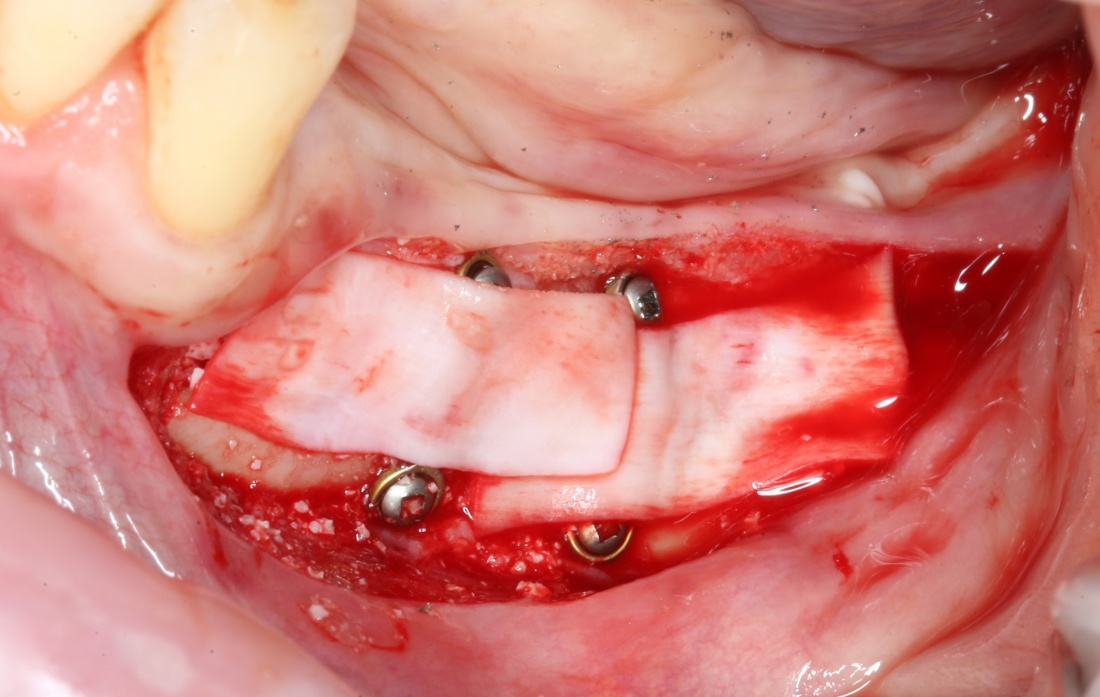

Я зафиксировал костный блок практически без адаптации на несколько винтов. Обрати внимание, что винты находятся в зоне, где не планируется установка имплантатов. Фиксация должна быть надежной, поскольку мне еще предстояла подготовка лунок для имплантатов. Трех винтов для этого вполне достаточно.

Дальнейшая адаптация костного блока свелась к сглаживанию острых краев. После чего я приступил к подготовке лунок и установке имплантатов.

Глянем на то, что получилось:

Осталось адаптировать костный блок (убрать острые края), проверить его фиксацию и, при необходимости, добавить винты. Десятисекундное дело.

Изоляция области аутографта и имплантатов барьерной мембраной.

Конкретно в этом клиническом случае между костным аутотрансплантатом, ложем и имплантатами есть пустое пространство. Если его не изолировать от мягких тканей, они прорастут и осложнят интеграцию аутографта. Поэтому я решил перекрыть костный блок барьерной мембраной, пусть это делает хирургическую операцию немного дороже.